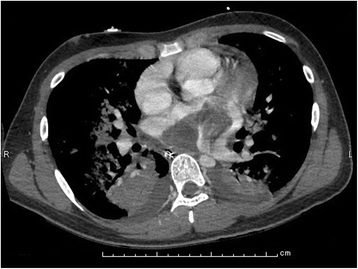

A butterfly glioma is most frequently a malignant glioma, but the butterfly description means that the tumor has crossed over the midline of the brain to involve both the right and left hemispheres.

Butterfly tumours are formed by primary cns lymphomas and diffuse astrocytomas). There may be other scans and tests that you will need to help diagnose your tumour. The images produced by a ct scan provide detailed information about. The scan creates detailed images of the blood vessels in the brain, which can help doctors plan surgery.